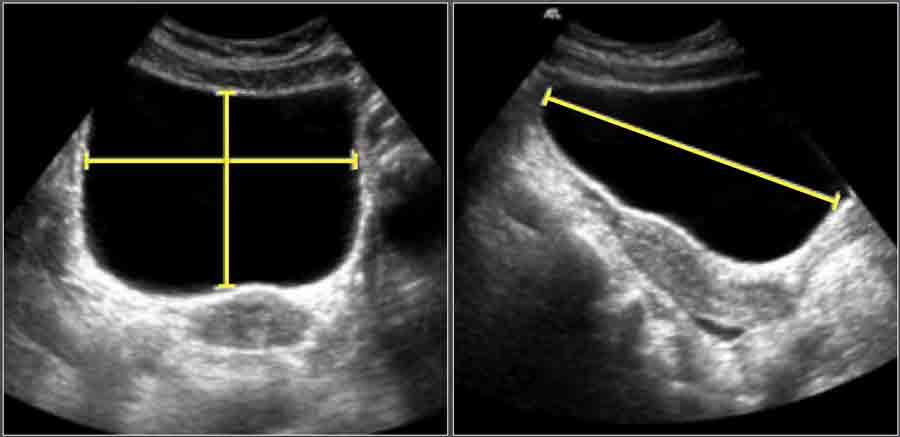

Kỹ thuật Đo lường

- Chiều dài (L): Đo trên mặt cắt dọc từ cổ bàng quang đến đáy bàng quang.

- Chiều sâu (D): Đo vuông góc với mặt phẳng dọc tại vị trí có diện tích mặt cắt ngang lớn nhất, từ bề mặt niêm mạc thành trước đến thành sau theo đường giữa.

- Chiều rộng (W): Đo vuông góc với D tại điểm giữa của D.

Tính toán Thể tích Bàng quang

Thể tích bàng quang được tính theo công thức hình elipsoid:

Thể tích (cm³) = L × D × W × 0,523